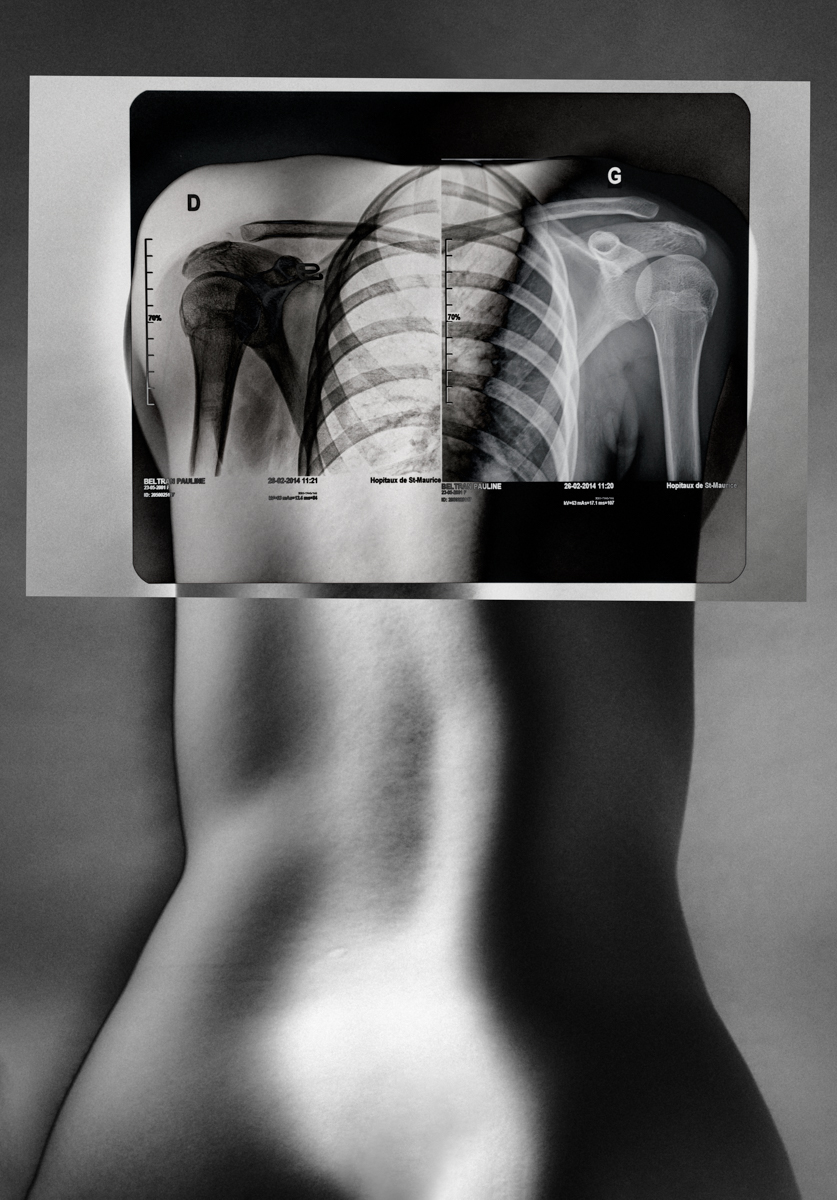

SURFACES SENSIBLES — À la frontière de l'autoportrait, "Surfaces sensibles" retranscrit une partie de ma réalité et brouille les limites entre l'intime anatomique et l'émotionnel.

La science produit les images les plus concrètes et les plus neutres pour illustrer les affects. Pourtant, par leur froideur et leur distance, elles sont les moins aptes à témoigner des émotions. Chaque radiographie, scanner, IRM correspond à une douleur ou à un mal-être spécifique.

Depuis peu, ces images ne sont plus seulement des réminiscences de douleurs passées, mais également des matériaux bruts inspirants pour ma pratique photographique. À partir des radios originelles, j'ai utilisé plusieurs techniques telles que la superposition et le tirage argentique dans le but de me rapprocher d'une perception alternative de ce corps irradié.